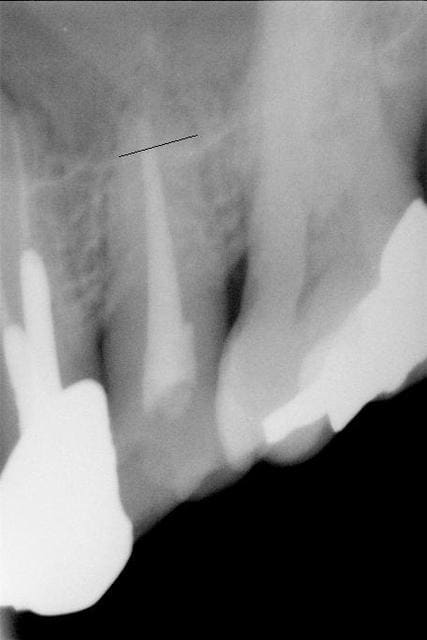

ci joint RX, je pense que c'est à peu près cette taille

du trait noir à l'apex au maximum peut être moins,

par contre j'ai fait une pano mais on ne voit rien au niveau

du sinus...

Radio 3D

C'est gros comme morceau...faut enlever.